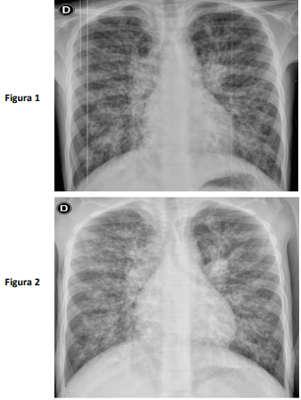

Paciente de 9 anos, sexo feminino, portadora de fibrose cística pancreato-insuficiente foi admitida no pronto-socorro queixando-se de tosse com aumento da expectoração de aspecto esverdeada, há uma semana; hoje, com pequena quantidade de sangue e sem febre associada. Em culturas prévias de escarro, apresenta colonização crônica para Pseudomonas aeruginosa, sensível aos antibióticos testáveis, e Staphylococus aureus resistente à meticilina. Já faz uso de oxigênio domiciliar, 1 L/minuto e nos últimos dias precisou aumentar para 2L/minuto. Ao exame clínico, paciente mantendo estado geral de base, alerta, hidratada, taquidispneica moderada, com crepitações difusas à ausculta. Saturação 94% em oxigênio 2L/minuto. Estável hemodinamicamente. A radiografia de tórax atual (figura 1) e no momento da alta na internação anterior (figura 2) estão apresentadas.

A paciente foi internada para suporte clínico com coleta de nova cultura de escarro. Com relação ao uso de antimicrobianos, podemos afirmar que a conduta adequada é: